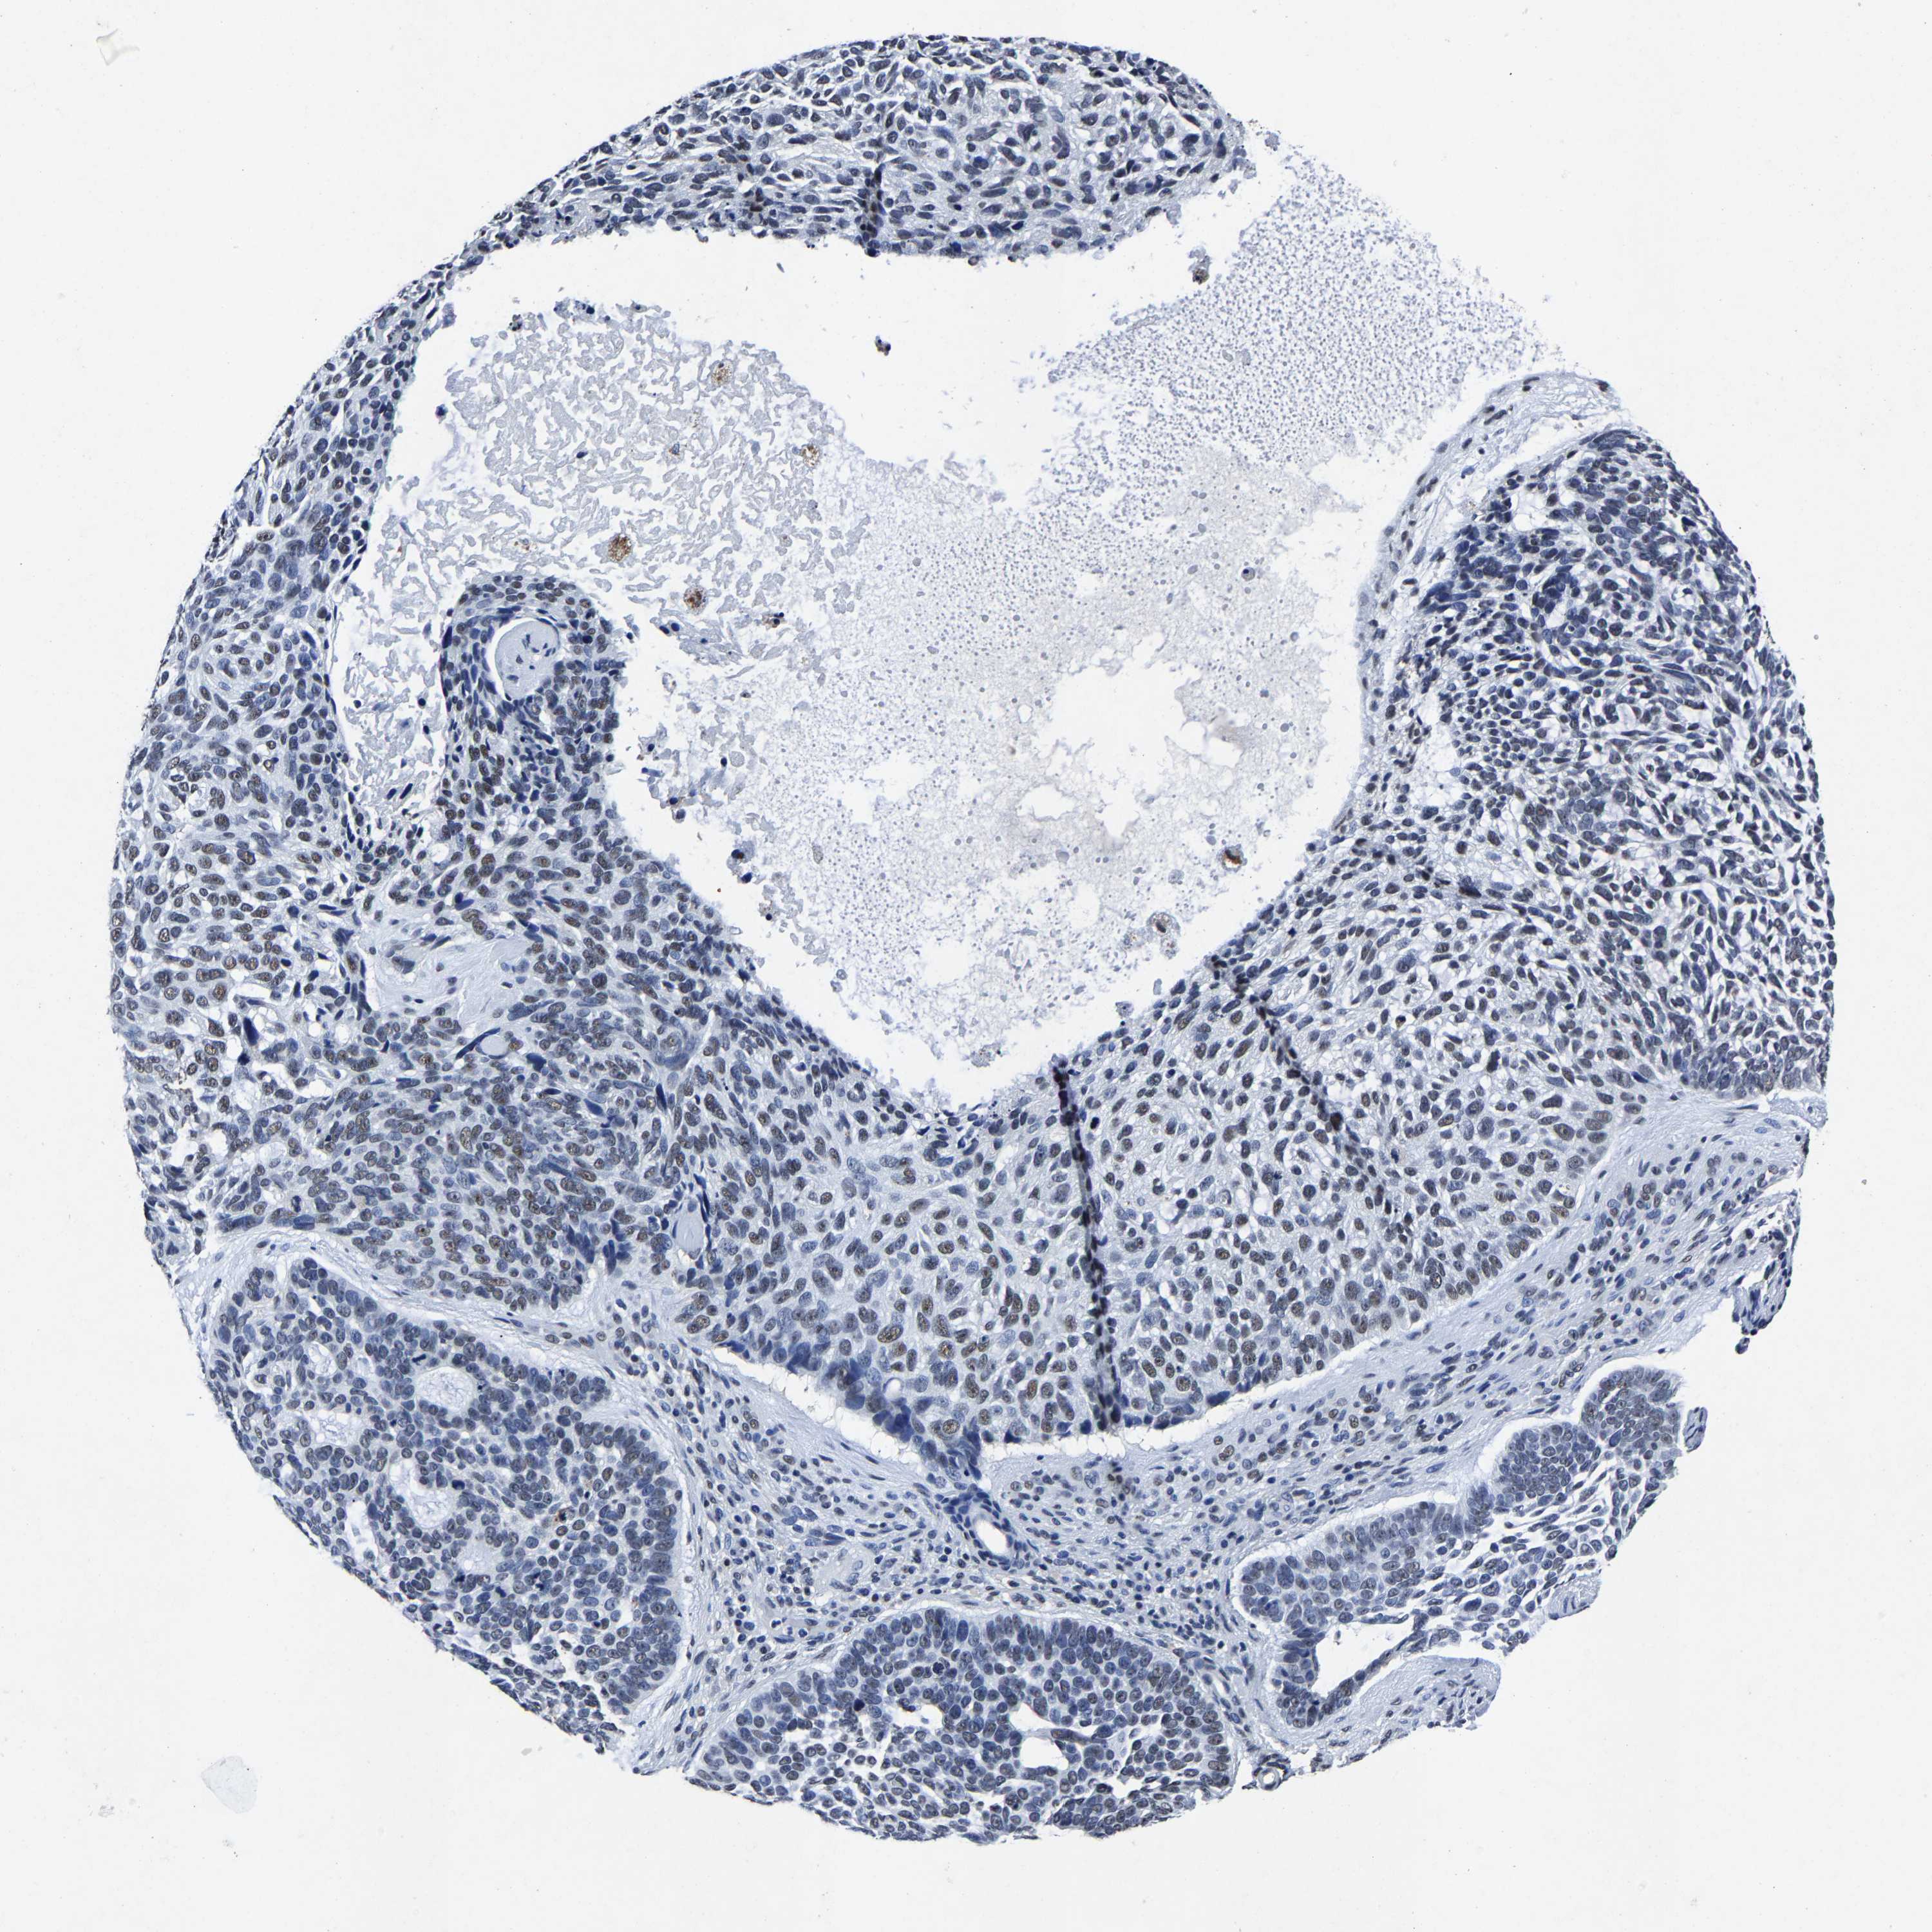

CANCER SKIN CANCER Show tissue menu

Basal cell and squamous cell cancer

SKIN CANCER - Protein expressioni

Antibody HPA020448

Staining

High

Intensity

Strong

Quantity

>75%

Location

Nuclear

Basal cell carcinoma